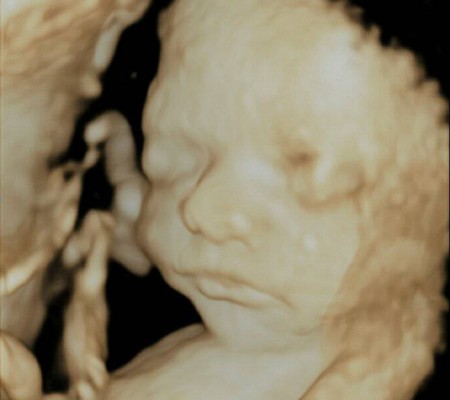

3D i 4D tehnologija omogućava da vidimo površinu bebe na lepši način i pokrete ploda u realnom vremenu.

Takođe nam omogućava da bolje vidimo fetalne mane na licu, šakama i stopalima.

Kao i 2D, 3D i 4D koriste ultrazvučni talas da se kreira slika bebe u materici. 3D je kreirana slika u prostoru dok 4D prikazuje pokret unutar materice pa možemo videti kako se beba smeje, mršti ili zeva.

Da bi se dobile dobre slike poželjno je da se pregled radi između 24 i 32 nedelje trudnoće.